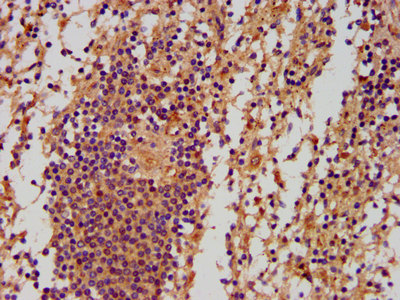

IHC image of CSB-PA773803LA01HU diluted at 1:500 and staining in paraffin-embedded human spleen tissue performed on a Leica BondTM system. After dewaxing and hydration, antigen retrieval was mediated by high pressure in a citrate buffer (pH 6.0). Section was blocked with 10% normal goat serum 30min at RT. Then primary antibody (1% BSA) was incubated at 4°C overnight. The primary is detected by a biotinylated secondary antibody and visualized using an HRP conjugated SP system.

IHC image of CSB-PA773803LA01HU diluted at 1:500 and staining in paraffin-embedded human appendix tissue performed on a Leica BondTM system. After dewaxing and hydration, antigen retrieval was mediated by high pressure in a citrate buffer (pH 6.0). Section was blocked with 10% normal goat serum 30min at RT. Then primary antibody (1% BSA) was incubated at 4°C overnight. The primary is detected by a biotinylated secondary antibody and visualized using an HRP conjugated SP system.